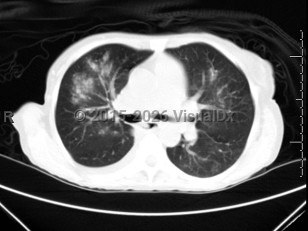

Imaging Studies image of Respiratory syncytial virus infection - imageId=6839039. Click to open in gallery.  caption: '<span>Axial CT image demonstrates bilateral (right worse than left) ground glass opacities with centrilobular nodules. Patient was positive for RSV.</span>'

Axial CT image demonstrates bilateral (right worse than left) ground glass opacities with centrilobular nodules. Patient was positive for RSV.